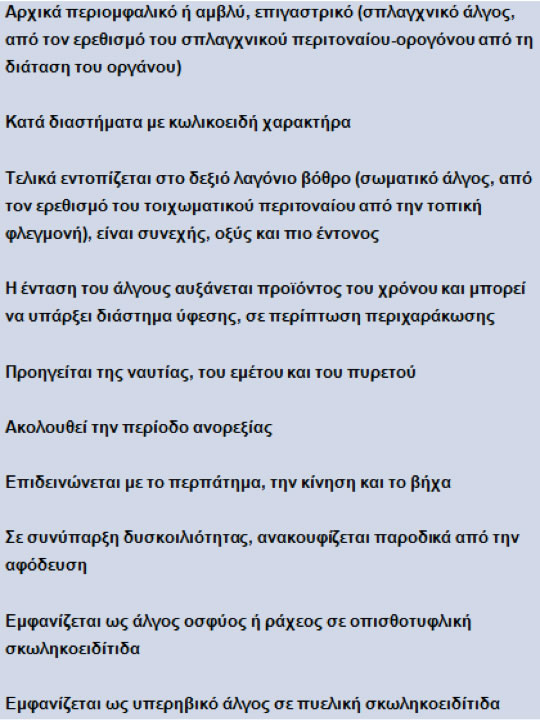

Προεξάρχον σύμπτωμα είναι το κοιλιακό άλγος, τα χαρακτηριστικά του οποίου συνοψίζονται στον Πίνακα 2.

Πίνακας 2.

Χαρακτηριστικά κοιλιακού άλγους στην οξεία σκωληκοειδίτιδα

Η τυπική κλινική εικόνα (60% των περιπτώσεων) χαρακτηρίζεται από ανορεξία, το περιομφαλικό άλγος, το οποίο αργότερα εντοπίζεται στο δεξιό λαγόνιο βόθρο, τη ναυτία, τον έμετο και την πυρετική κίνηση.

Ανορεξία: το πιο σταθερό πρόδρομο σύμπτωμα, εμφανίζεται τα τελευταία 24ωρα πριν από τον πόνο. Μπορεί να μην υπάρχει στα παιδιά.

Ναυτία και έμετος: συνήθως μικρής ποσότητας, συνοδεύουν ή ακολουθούν τον πόνο. Δεν είναι έντονα σε οπισθοτυφλική.

Πυρετός: υπάρχει σε κάθε οξεία σκωληκοειδίτιδα, δεν υπερβαίνει συνήθως το 380C. Σε γάγγραινα και διάτρηση: υψηλότερος και συνοδεύεται από ρίγος.

Δυσκοιλιότητα: αναφέρεται συχνά, ο ασθενής ανακουφίζεται με την αφόδευση.

Διάρροια: σε πυελική σκωληκοειδίτιδα ή σε δημιουργία πυελικού αποστήματος μετά από διάτρηση της σκωληκοειδούς.